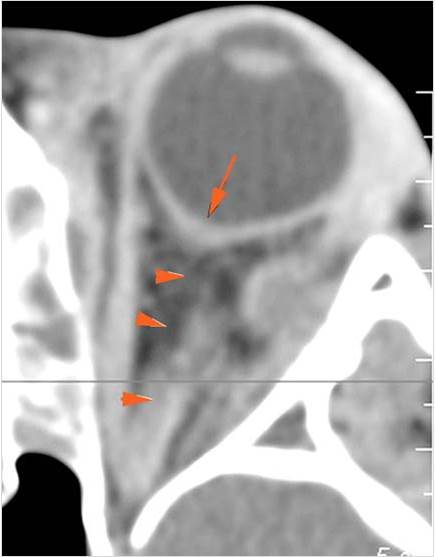

Sinuses

There is soft tissue swelling anterior to the frontal sinus or in the soft tissues surrounding the maxillary sinuses.

There is mucoperiosteal thickening in the sinuses.

There is mucosal enhancement in the sinuses.

There is bone erosion along the walls of any affected sinuses.

There is an appearance of bone expansion, due to regressive remodeling and suggestive of pre-existing mucocele, along the walls of any affected sinuses.

Orbits

The extraconal orbital fat is abnormal.

There is a subperiosteal abscess or edema along the medial wall, roof or floor of the orbit.